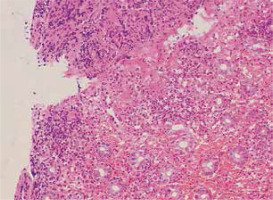

Small intestinal endoscopy findings

Endoscopic examination demonstrated diffused hyperemia, dropsy and erosion in the inferior segment of the ileum (Fig. 3A). And a ring-shaped ulcer was also seen in the small intestine (Fig. 3B). Pathologic examination revealed extravasation of red blood cells with mild inflammation. In addition, the examination clearly delineated a great quantity of neutrophilic leukocyte infiltration in mucosa and sub-mucosa, and obvious bleeding points in mucosa (Fig. 4).

Therefore, we also conducted abnormal contrastenhanced CT and small intestinal enteroscopy for patients. The contrast-enhanced CT examination of the abdomen showed the intestinal canal wall thickening and edema. Endoscopic examination demonstrated diffused hyperemia, dropsy and erosion in the inferior segment of the ileum. And a ring-shaped ulcer was also seen in the small intestine. By combining the results of abnormal contrast-enhanced CT with small intestinal enteroscopy examination findings, we can diagnose the abdominal characteristics of patients.